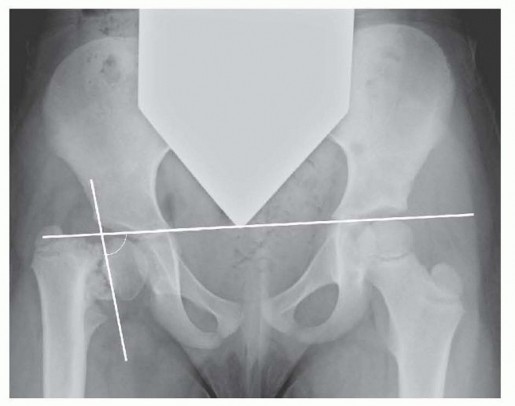

Innominate Osteotomy of Salter DEFINITION The Salter innominate osteotomy is commonly performed in conjunctio…